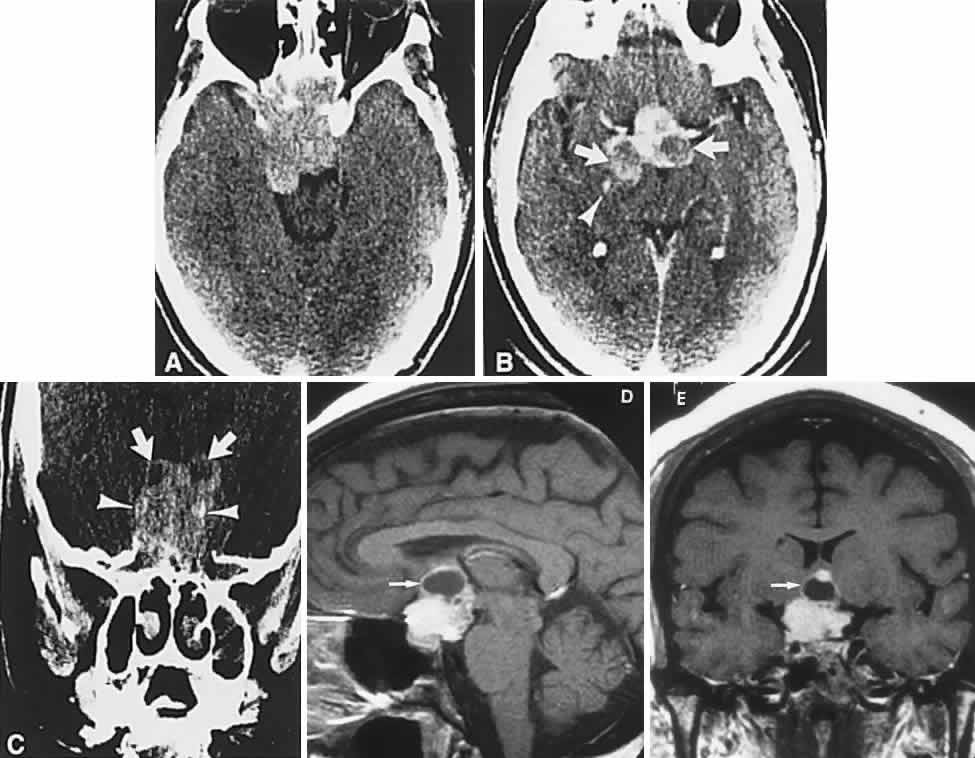

CT scanning retains special relevance to craniopharyngioma diagnosis, currently superior to MRI in detection of calcification and cyst formation (Fig. 7A to C); however, the extent of involvement of adjacent structures, that is, the optic chiasm, third ventricle, and intracavernous carotid artery, is more clearly delineated by MRI (Fig. 7D and E).93 Craniopharyngioma fluid collections are found to be uniformly bright on T2-weighted sequences, but on T1-weighted images, the signal intensity may range from hypointense to hyperintense, reflecting the heterogeneous contents of cysts. Because calcification and cyst formation are hallmarks of craniopharyngiomas, CT is more specific than MRI. At times, intrinsic infiltration of tumor may thicken the chiasm and contiguous optic nerve, a radiologic configuration that mimics glioma.94 Likewise, glioma may be simulated when the optic canal is invaded and enlarged, but accompanying bony erosion of the sella weighs heavily toward craniopharyngioma.

Fig. 7. Computed tomography scan of a large, multicystic craniopharyngioma. A. Axial section through the sella shows destruction of the bony skull base. Axial (B) and coronal (C) sections show cysts (white arrows) and calcification (arrowheads). Contrast-enhanced magnetic resonance imaging of the craniopharyngioma. Sagittal (D) and coronal (E) sections with gadolinium show solid and cystic (arrows) portions.